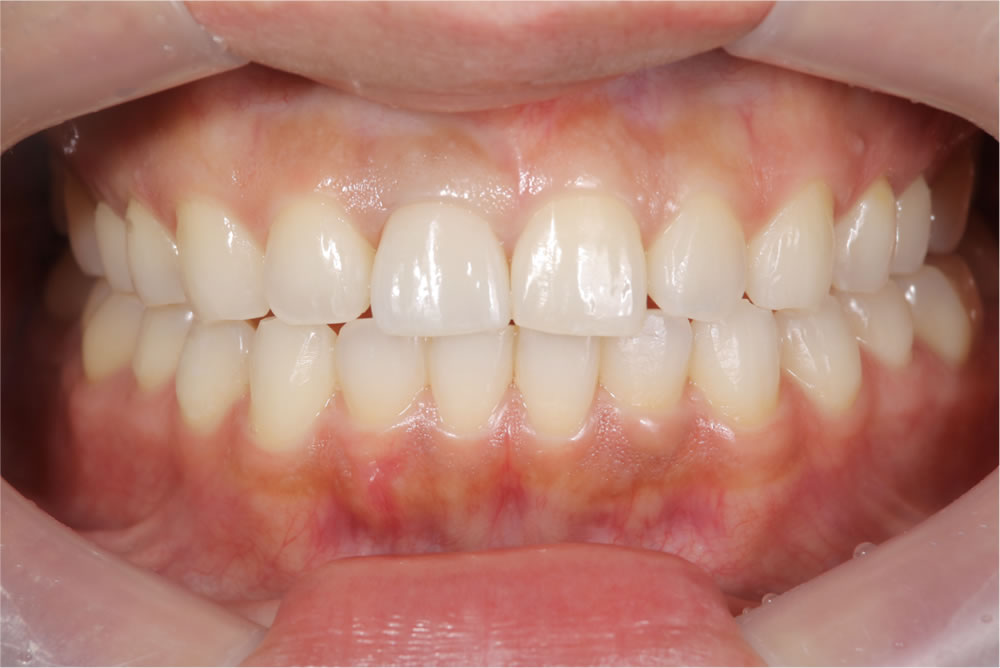

最終のインプラントの上部構造(ジルコニア)を装着

最終のインプラントの上部構造(ジルコニア)を装着し、咬み合わせを調整しました。

ホワイトニングで「口元全体」を仕上げる

前歯1本だけが綺麗でも、周囲の歯との色が合っていなければ違和感が残ります。

そこで、仮歯の期間中にホワイトニングを実施しました。口元全体のトーンを整え、「作った歯」ではなく「もともとこうだった」ような仕上がりを目指しました。